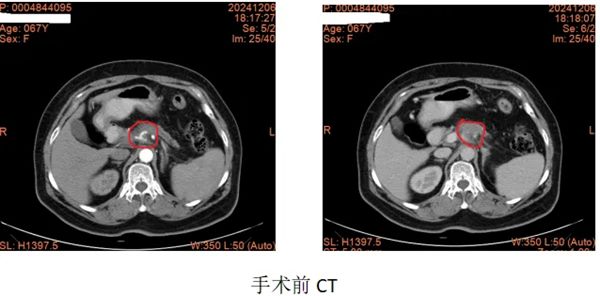

该患者来自河北省,6个月前因左上腹部疼痛进行MRI检查提示:胰颈部占位,考虑胰腺癌可能性大,同层面脾动脉、脾静脉及腹腔干受侵可能性大。经过2个月艰辛的求医之路,疗效甚微。2024年9月,慕名来到郑大五附院李晓勇教授门诊,经过李教授的认真阅片及详细查体,考虑局部进展期胰腺癌,入院后请肿瘤内科、消化内科、影像科、临床营养科等相关科室行MDT讨论,共同制定治疗方案:按“AG d1,8天 q21天”方案化疗,化疗后若肿瘤缩小,行纳米刀消融术。经过“AG”方案4疗程的化疗,影像学检查提示肿瘤明显缩小,Ca19-9降至正常。经过李晓勇教授、陈艳军主任医师带领科室再次详细回顾患者病史、查体及治疗经过,一致同意为患者进行胰腺肿瘤纳米刀消融术。

2024年12月,在手术部•麻醉科胡强夫主任麻醉团队及手术室刘丹丹护士长护理团队的配合下,在超声影像科杨青主任团队精准的超声引导下,李晓勇教授、陈升阳医生团队为患者实施超声引导下经皮胰腺癌纳米刀消融术。术后皮肤仅有数个穿刺针眼。经过林磊护士长团队精心护理,患者恢复顺利出院,治疗后腹痛完全缓解,饮食恢复至正常,肿瘤标志物降至正常。目前已完成术后第1疗程化疗治疗。